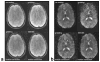

The correction of motion artifacts continues to be a significant problem in MRI. In the case of uncooperative patients, such as children, or patients who are unable to remain stationary, the accurate determination and correction of motion artifacts becomes a very important prerequisite for achieving good image quality. The application of conventional motion-correction strategies often produces inconsistencies in k-space data. As a result, significant residual artifacts can persist. In this work a formalism is introduced for parallel imaging in the presence of motion. The proposed method can improve overall image quality because it diminishes k-space inconsistencies by exploiting the complementary image encoding capacity of individual receiver coils. Specifically, an augmented version of an iterative SENSE reconstruction is used as a means of synthesizing the missing data in k-space. Motion is determined from low-resolution navigator images that are coregistered by an automatic registration routine. Navigator data can be derived from self-navigating k-space trajectories or in combination with other navigation schemes that estimate patient motion. This correction method is demonstrated by interleaved spiral images collected from volunteers. Conventional spiral scans and scans corrected with proposed techniques are shown, and the results illustrate the capacity of this new correction approach.